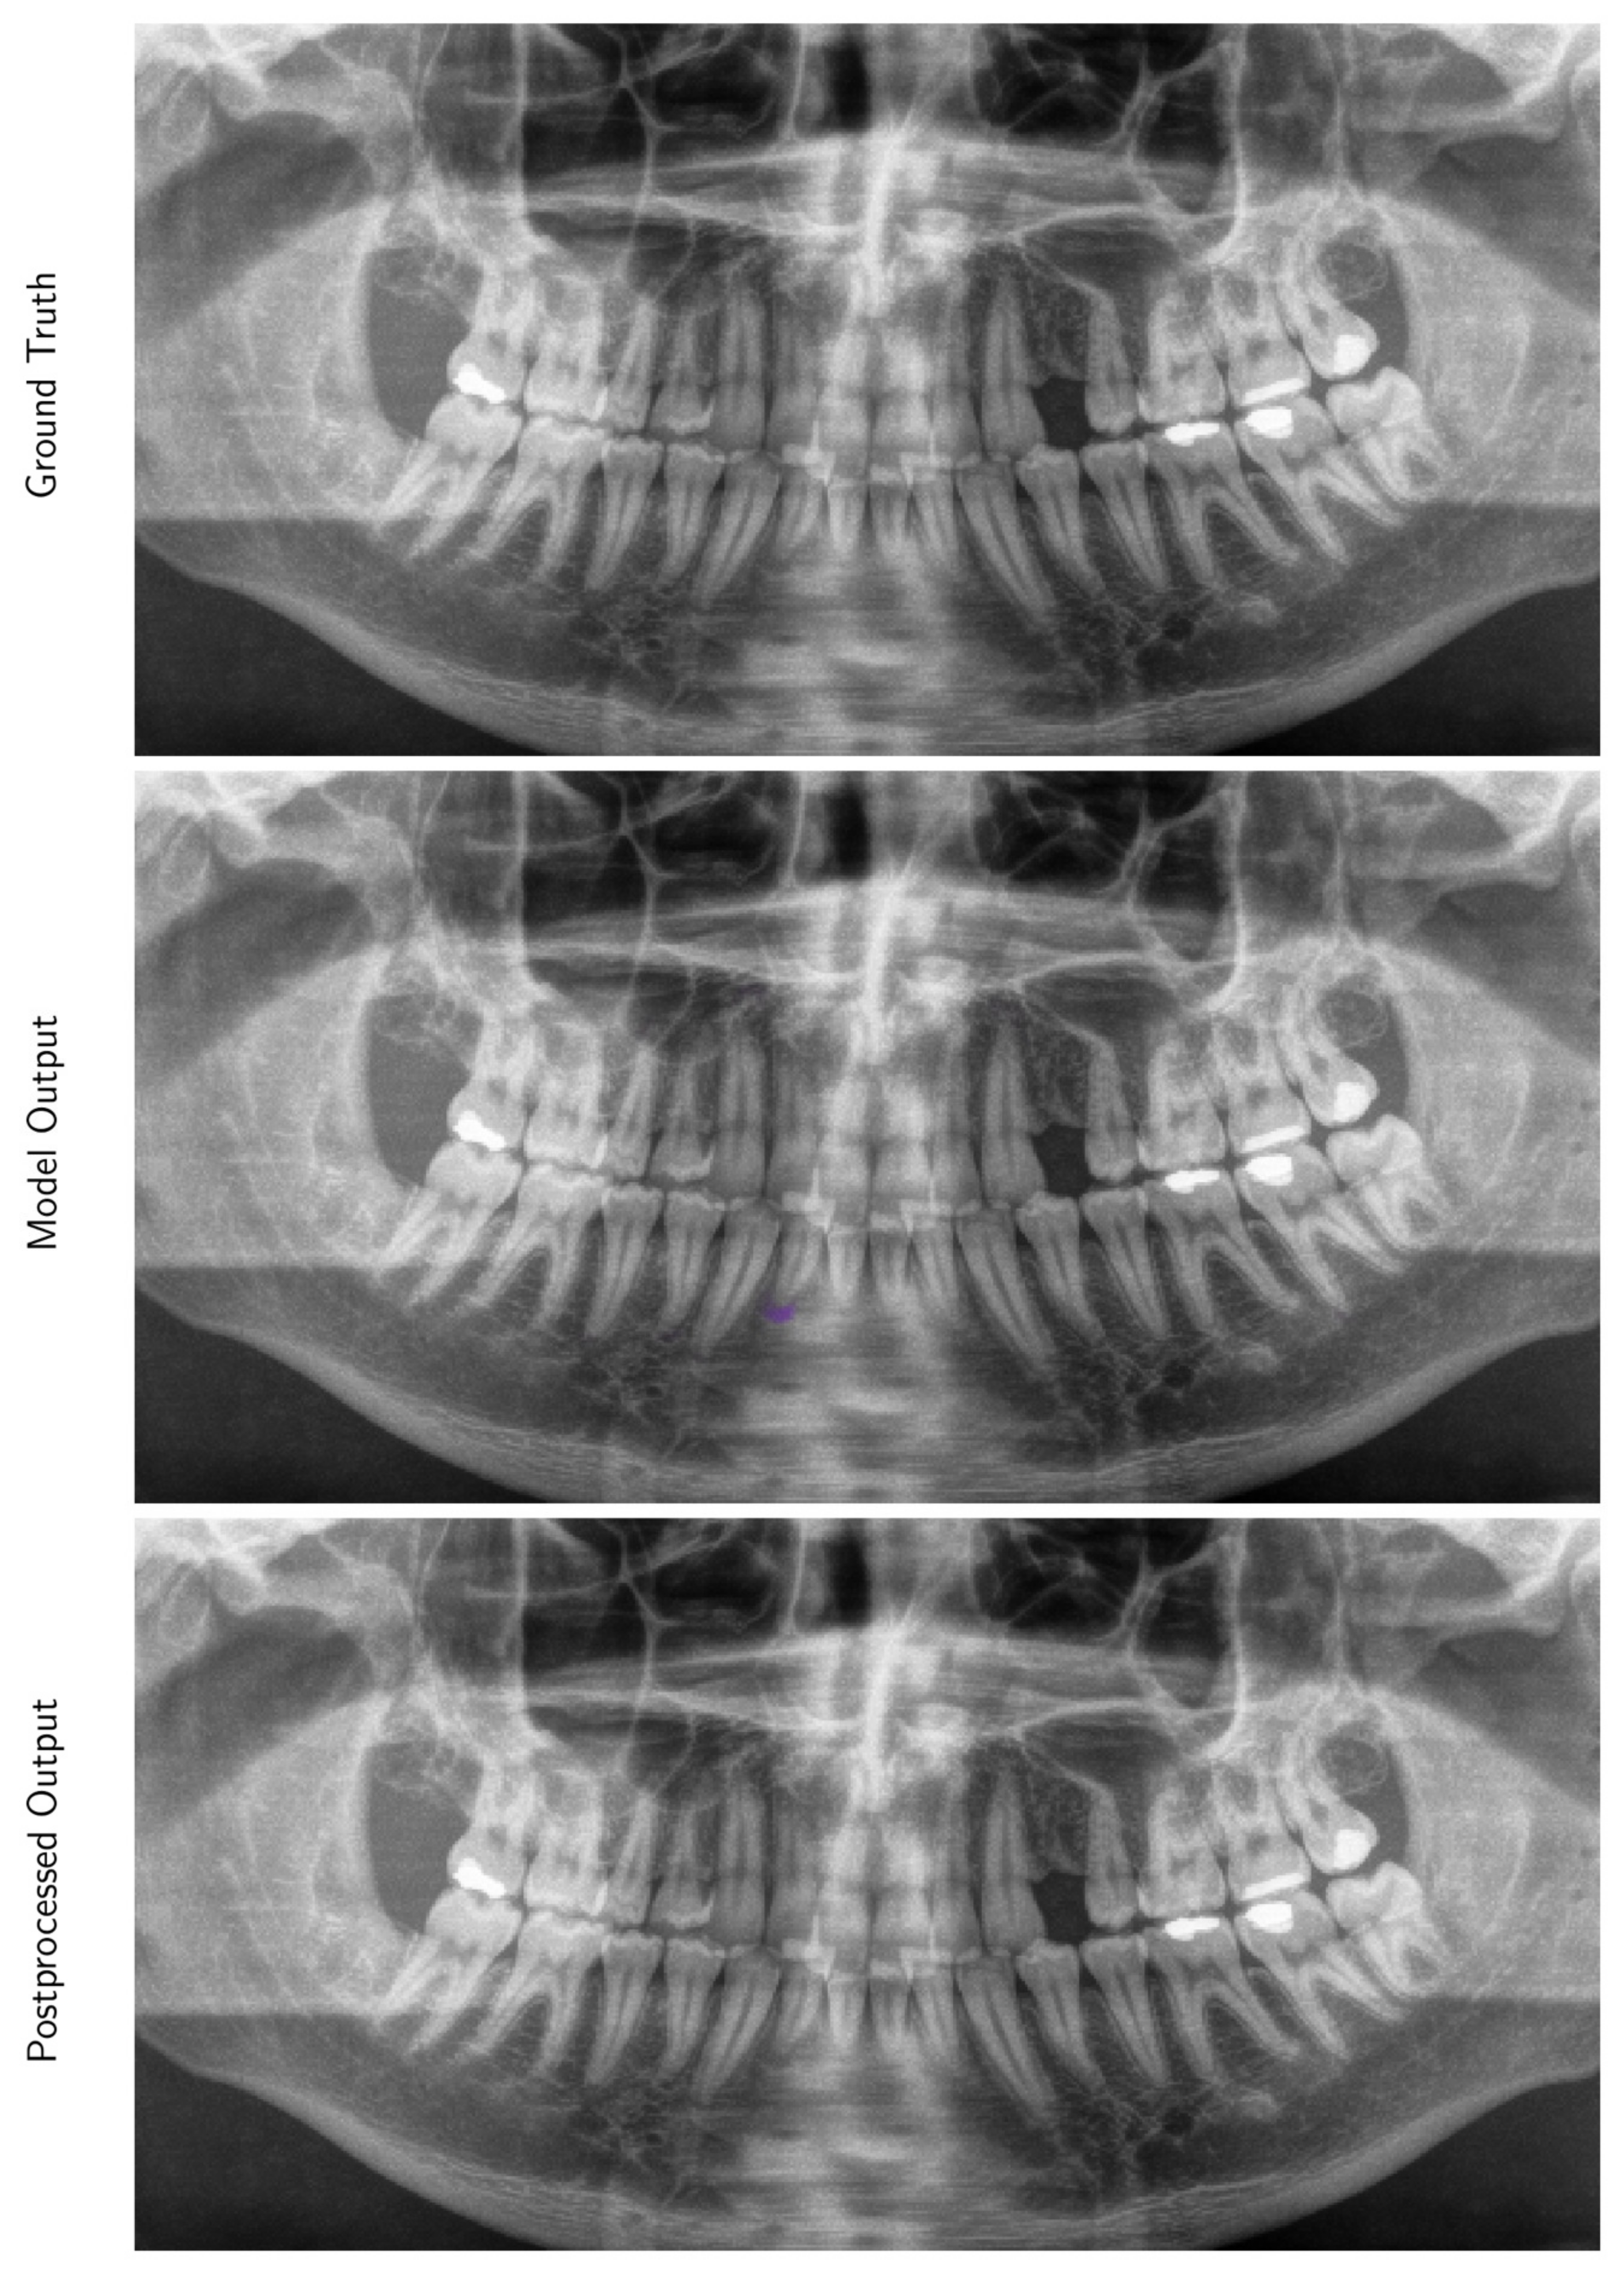

3.2. Performance of the Deep Learning Algorithm